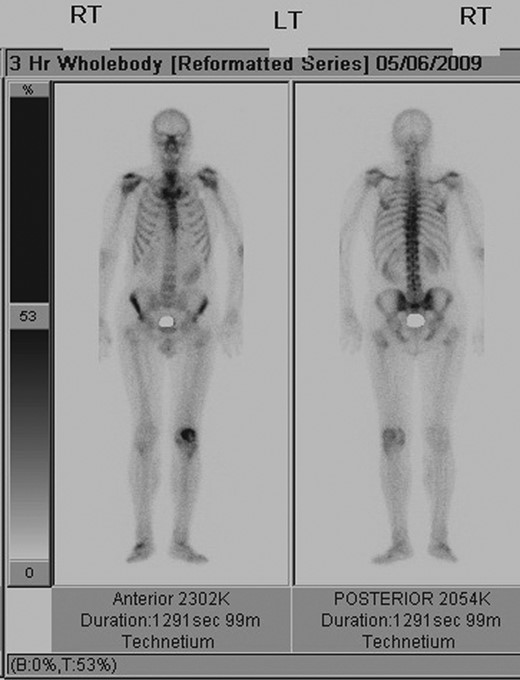

Repeat radiographs performed by his general practitioner 19 months after initial presentation (Figs 4–6) revealed a large lucency within the patella and a discontinuity in the anterior cortex of the inferior pole suggesting pathological fracture. A bone scan was arranged and demonstrated isolated abnormal tracer activity around the left patella (Fig. 7). Due to the pacemaker a computed tomography (CT) scan was performed to further characterize the lesion. This confirmed a large lucent area occupying most of the patella with multiple areas of cortical disruption along its anterior border (Fig. 8). Since the exact nature of the lesion could not be determined an ultrasound-guided biopsy was suggested but ultrasound screening revealed the lesion to be highly vascular (Fig. 9). In view of this the radiologist performed a renal ultrasound, which revealed a large mass arising from the superior pole of the left kidney. Subsequent CT of the chest, abdomen and pelvis followed demonstrating the extent of disease. There was a large (13 × 8.5 × 9 cm) mass arising from the superior pole of the left kidney (Fig. 10), the appearances of which were consistent with a primary RCC. Metastases were found in both adrenals and lungs, but no other bone metastases. Since diagnosis, the patient has had a left nephrectomy and is currently receiving radiotherapy and zolendronic acid treatment for the patella metastasis. At the time of writing this report the patient's patella lesion continues to be managed non-operatively.

Whole-body bone scan demonstrating isolated increased tracer uptake around the left patella.